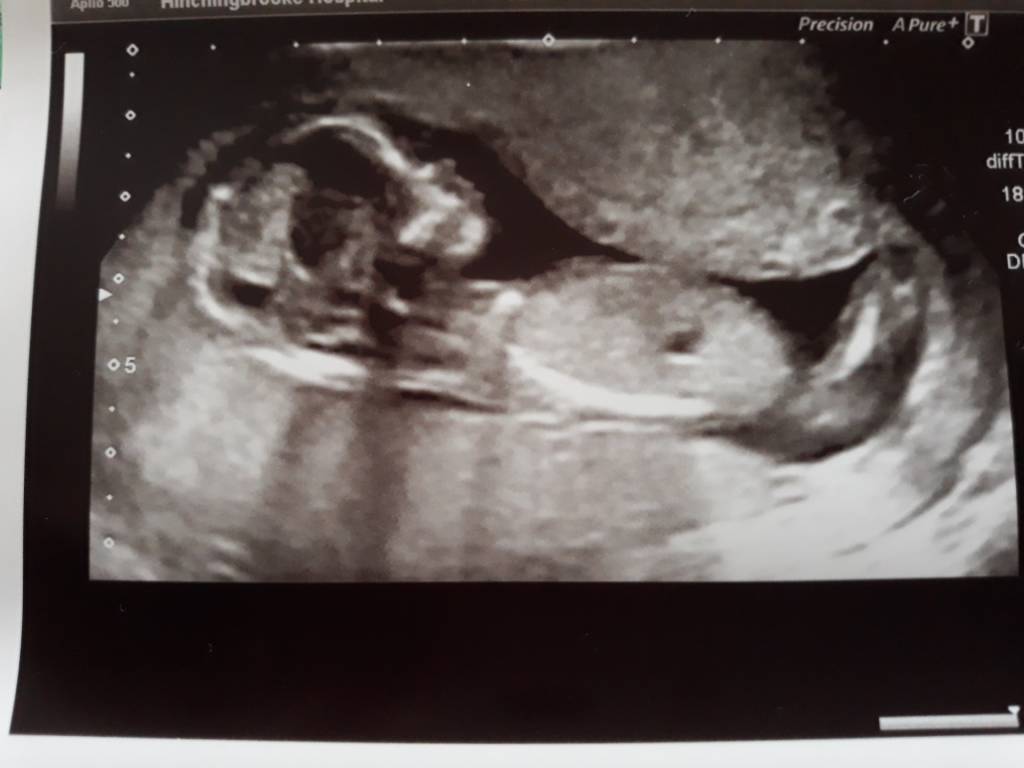

Tak wiec wizyta z 29.09 - gdy mój bobasek miał 13 t 2d.

Ktos dopatrzył sie ze ssie kciuk![]()